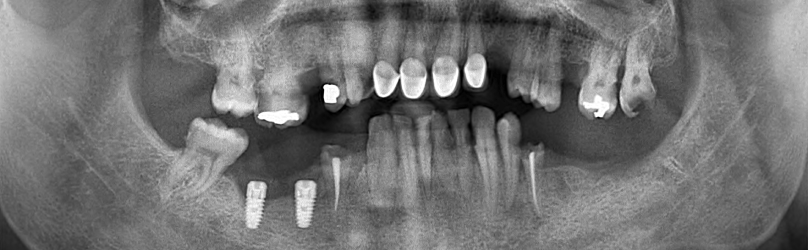

Images radiographiques

La première étape du processus de traitement consiste à prendre des images radiographiques détaillées. Ces images aident à déterminer le plan de traitement le plus approprié en évaluant la structure de votre mâchoire et votre santé dentaire. Nos radiographies révèlent à quel point le processus de traitement est extrêmement minutieux.